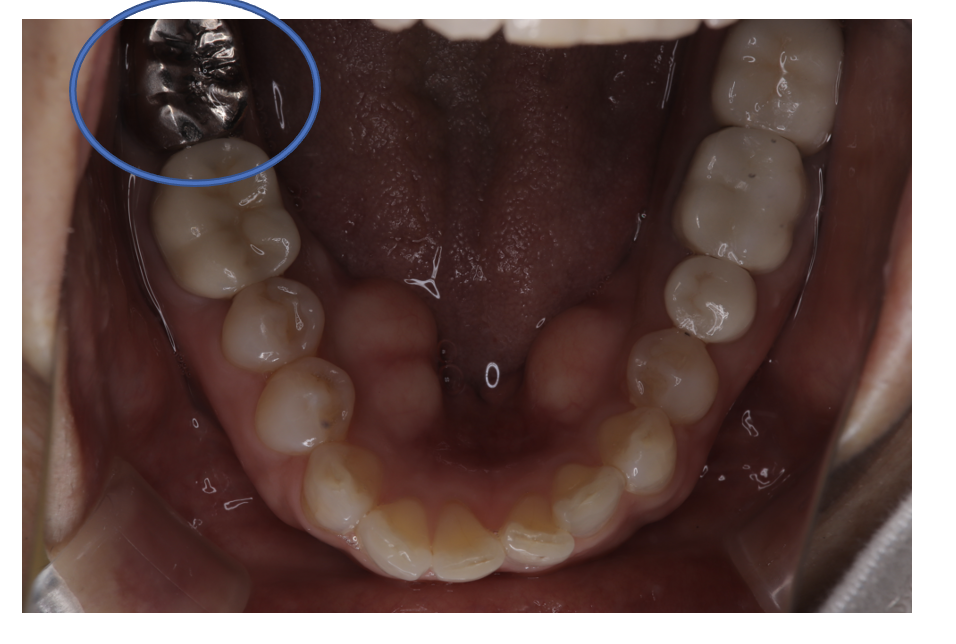

クラウンフルジルコニア

フルジルコニアCr 29 No.74

Before

After

| 治療方法 | フルジルコニアCr 虫歯などで失った歯質を天然歯と同じ色・質感のセラミックの一種であるジルコニア(人工ダイヤモンド)で補う治療法。 |

| 治療のデメリット | 変色がなく耐久性の高い治療ですが、歯周病や二次虫歯を予防するためには歯科医院での定期的なメインテナンスが大切です。 |

| 費用 | ¥89,000 |

| 通院回数 | 1ヶ月〜6ヶ月 |

| 備考 | 院長より 銀歯の内部に虫歯が進行してしまっていたケースです。中を開けて見てみると、外から想像するよりもはるかに虫歯が広がってしまっていました。幸運にも神経を保存できたので、生きた臓器としてまだ使うことが可能です。残存歯質がかなり薄く弱くなってしまったので、ジルコニアで被せて守ってあげています。しっかりとした治療ができたので、まだまだ長く使っていけるでしょう。 |